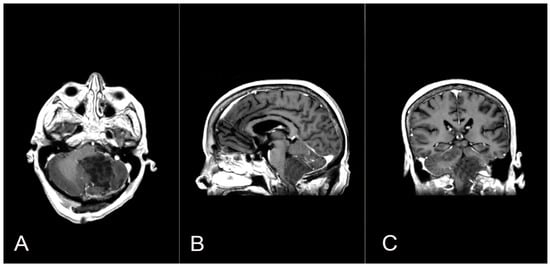

Figure 5.

A second surgery was performed through a telo-velar approach, and postoperative contrast-enhanced brain MRI (A,B) is shown. The lesion intraoperatively appeared to be a calcified mass tenaciously attached to contiguous structures, and a portion of the tumor was found to be tightly adherent to the left lateral recess, which was left in situ after a positive irritative response during the neurostimulation of the XII cranial nerve.